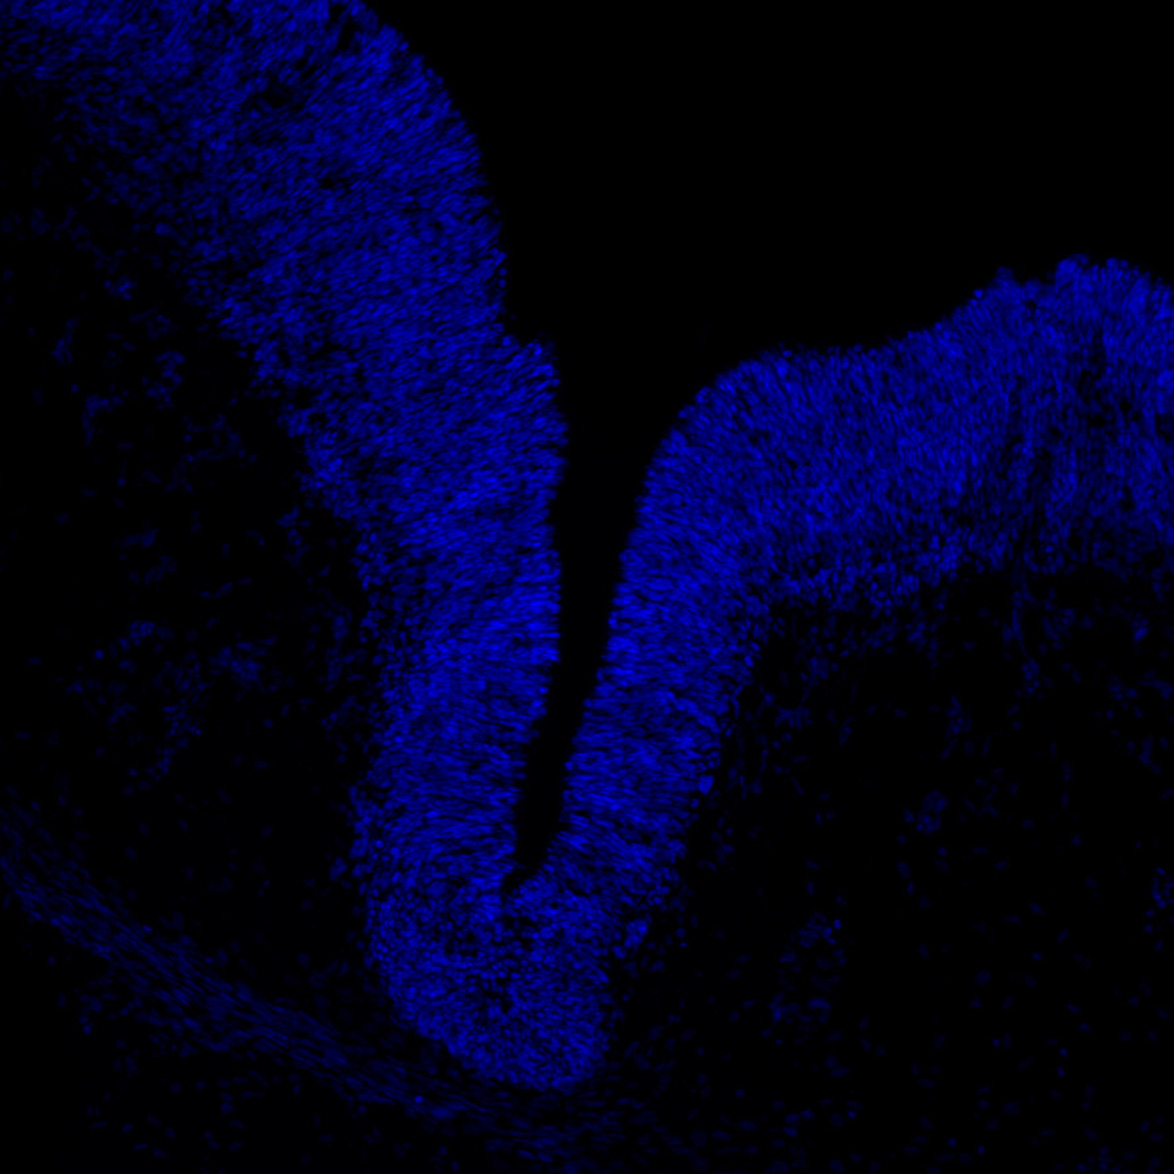

DAPI

6PCW human midbrain